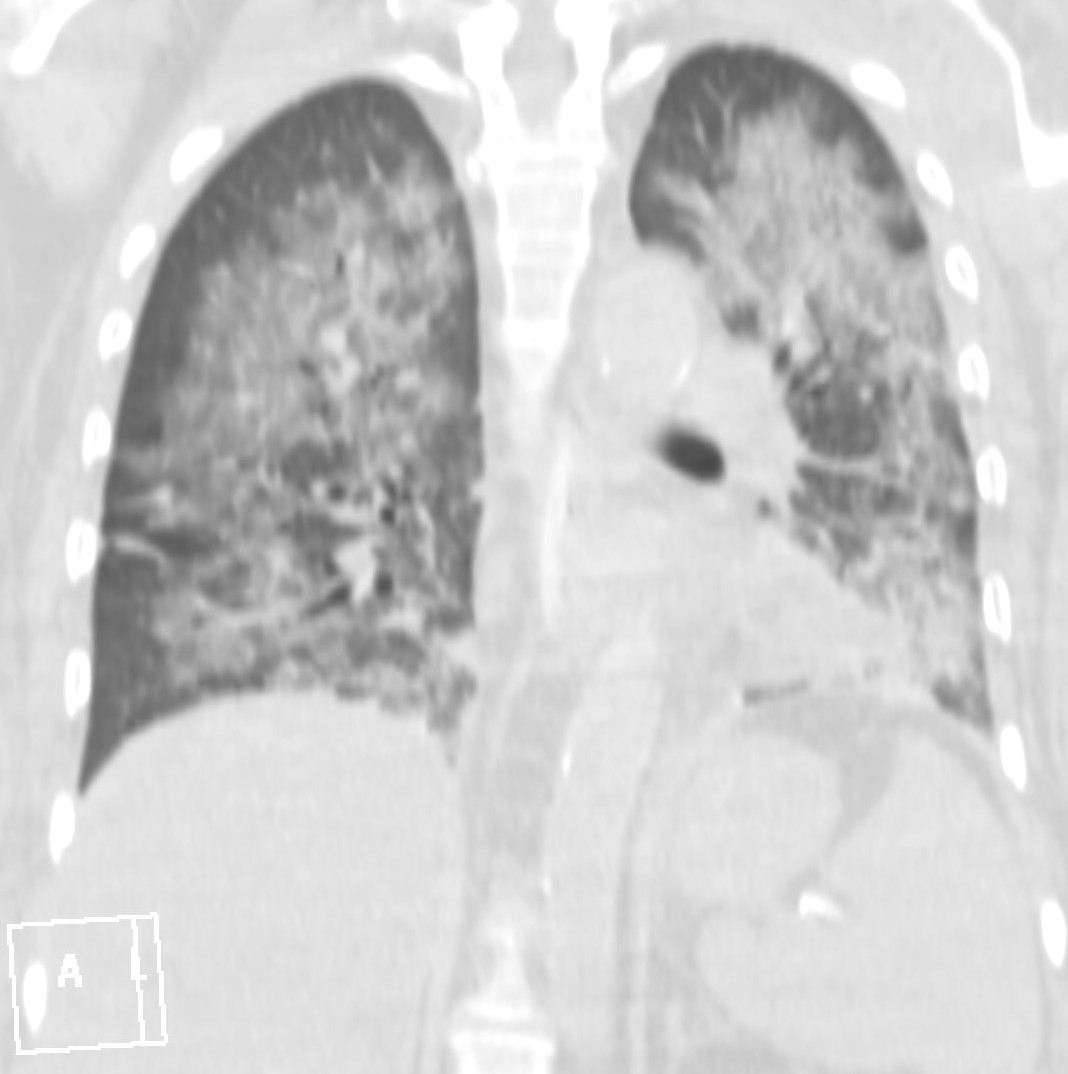

26. ARDS, CT, coronary reconstruction

52 year old woman, dyspnea, septic shock.

Bilateral opacity according to rough, diffuse interstitial edema, irregular atelectasis and bronchogram in the basal segments